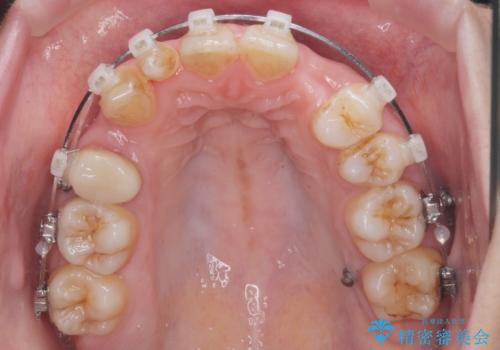

- 矯正装置

- ワイヤー矯正

- 治療期間

- 3年

- 治療回数

- 30回以上

矯正治療で歯並びを治した後、乳歯を抜いたところにブリッジを入れています。